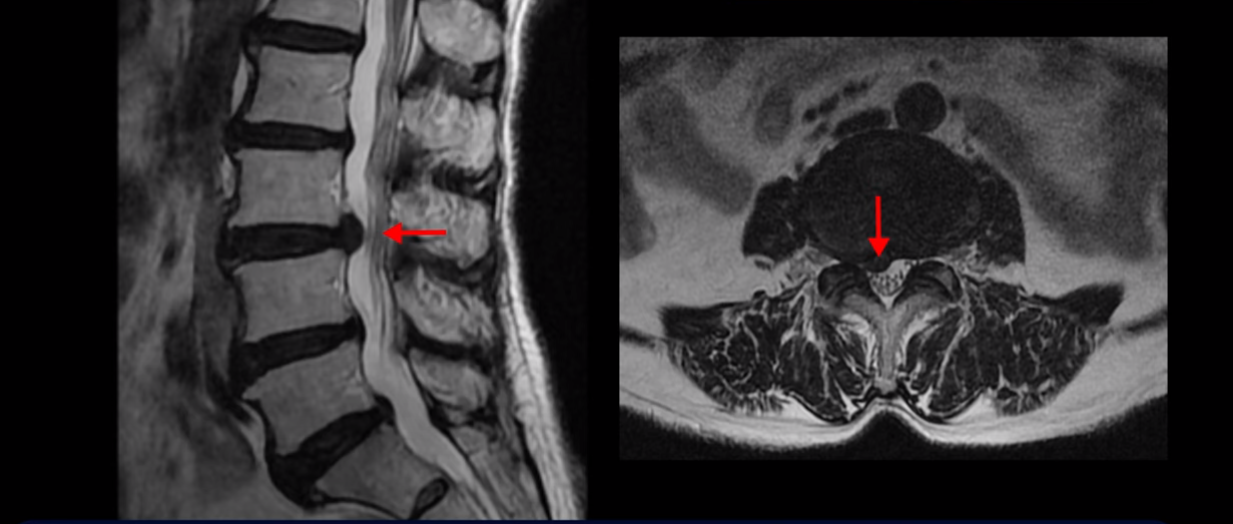

하지만 이 디스크 파열은 오래된 걸로 보이며, 지금 이 환자분의 아픈 양쪽 다리 특히 양쪽 발의 통증, 발 시린 증상과는 관련이 없어 보입니다. 오른쪽 왼쪽의 신경가지가 빠져나가는 추간공을 보면 오른쪽은 5번 1번과 4번 5번이 많이 좁아져 있고

왼쪽은 5번 1번이 많이 좁아져 있습니다.

이렇게 오른쪽 왼쪽 양쪽 추간공들이 다 좁아져 있고 신경가지들이 눌려있으니까 양쪽다리와 양쪽 발이 저리고 시리고 아파서 걷기 어렵습니다. 그런데 이 환자분은 신경주사를 여러 번 맞아도 듣지를 않는데요. 이렇게 신경주사가 듣지 않으면 십중팔구 수술밖에 방법이 없다는 얘기를 듣습니다. 그럼 어떻게 이런 신경이 눌려있는 환자분들을 수술 없이 치료해서 잘 걷게 만들고 다리와 발이 저리고 시리고 아픈 증상이 사라지게 만들까요? 지금부터 설명해드립니다.